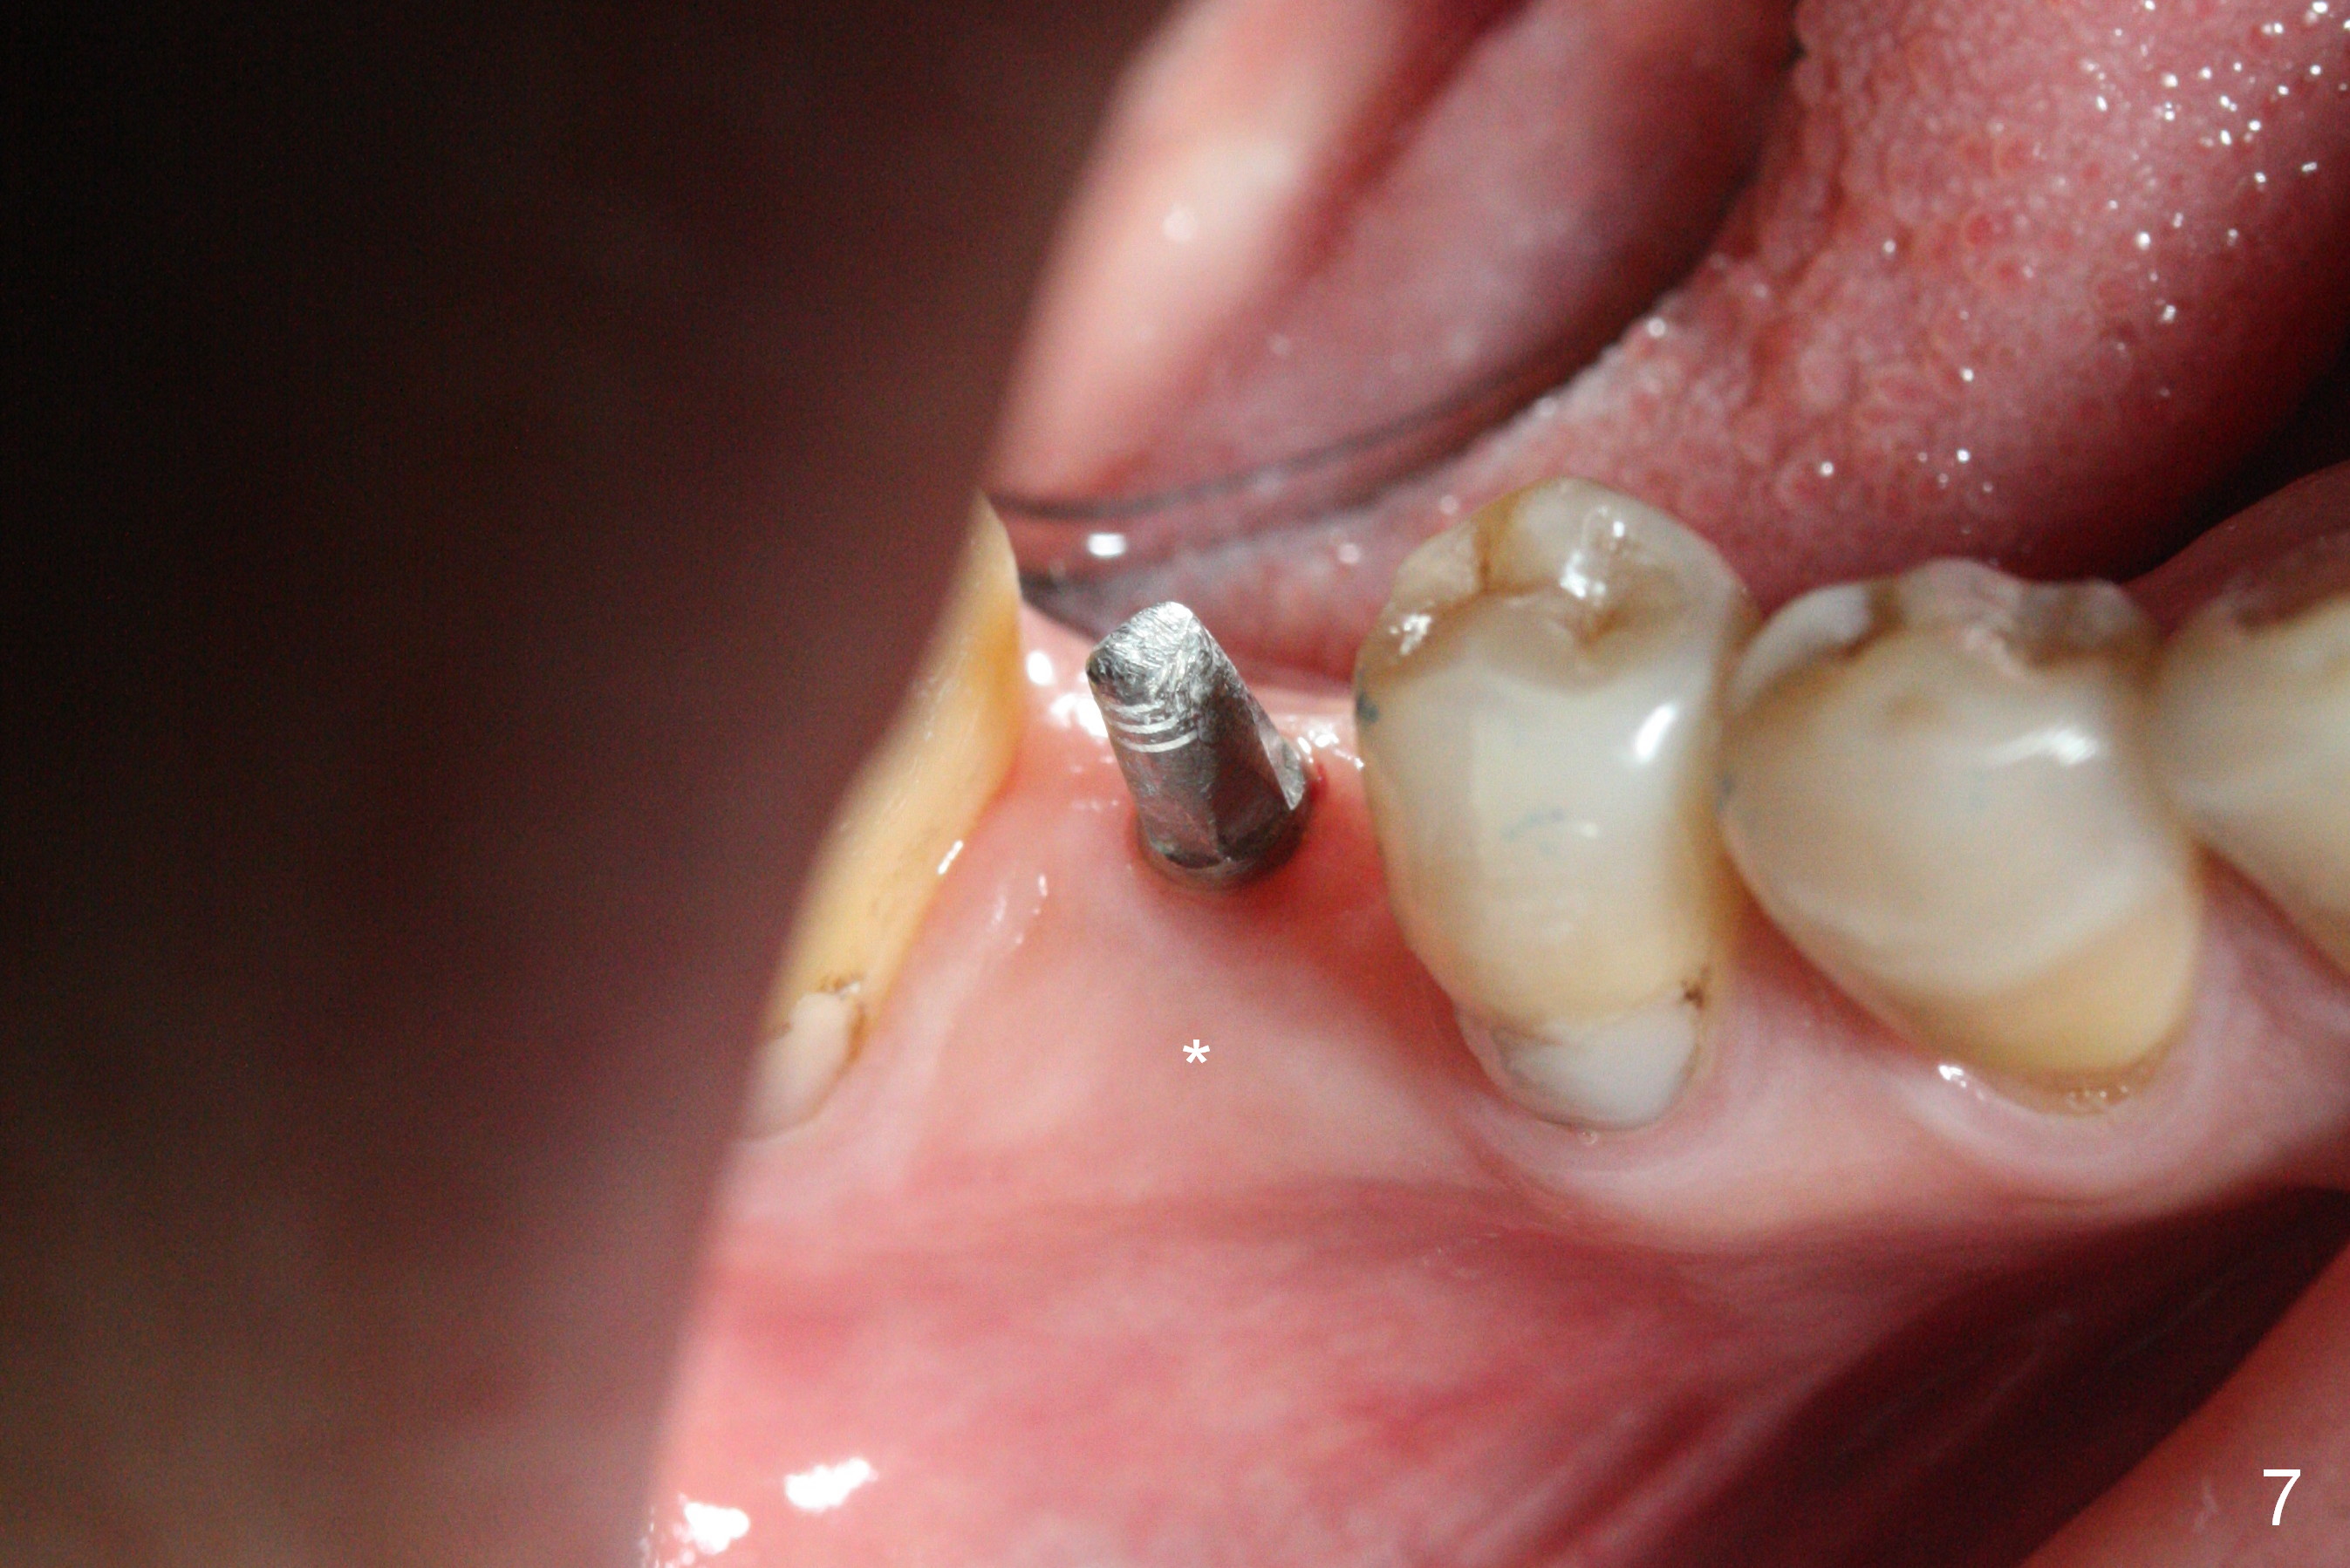

Before crown cementation, the ridge looks wider (Fig.7 *) than preop. There is no diastema between #31 and 32 (Fig.8, 17 days post cementation). The patient is pleased with less food impaction. The total treatment (including ortho) is 16 months. It appears that distalization of #29 is not effective to gain the bone width. In fact simultaneous GBR with implant placement is much more efficient. There is no bone loss 3 months post cementation (Fig.9). The gingiva looks healthy 10 months post cementation (Fig.10). The implant crown is functioning 1 year 9 months post cementation (Fig.11) and 3 years 7 months post cementation (Fig.12).